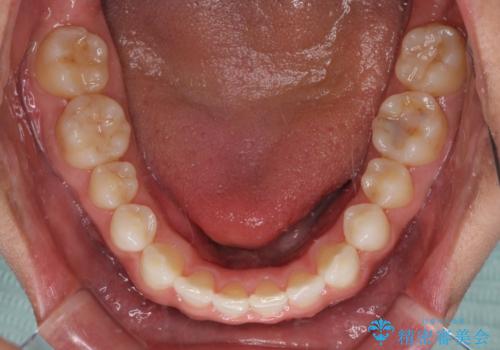

- 上下前歯のデコボコを気にして来院された患者様です。

以前矯正をした後戻りということで、歯列不正はそれほど大きくなかったため、インビザライン・ライトを用いて矯正治療を行うこととしました。